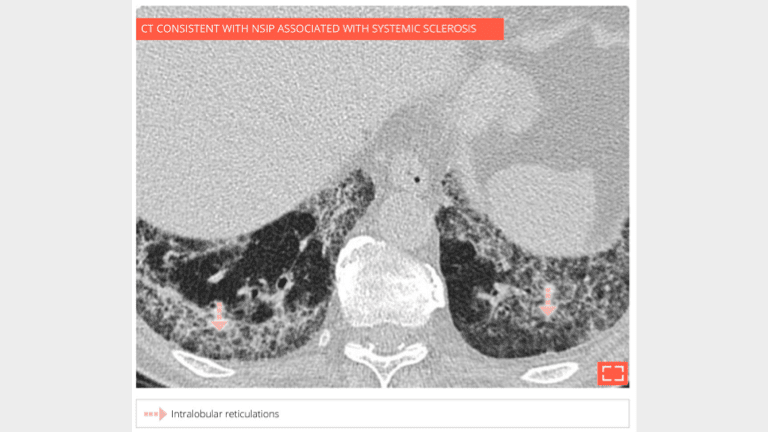

Marked intralobular reticulations in the 2 lung bases without honeycombing. Note the relative lung savings immediately under pleura, pointing to a NSIP.